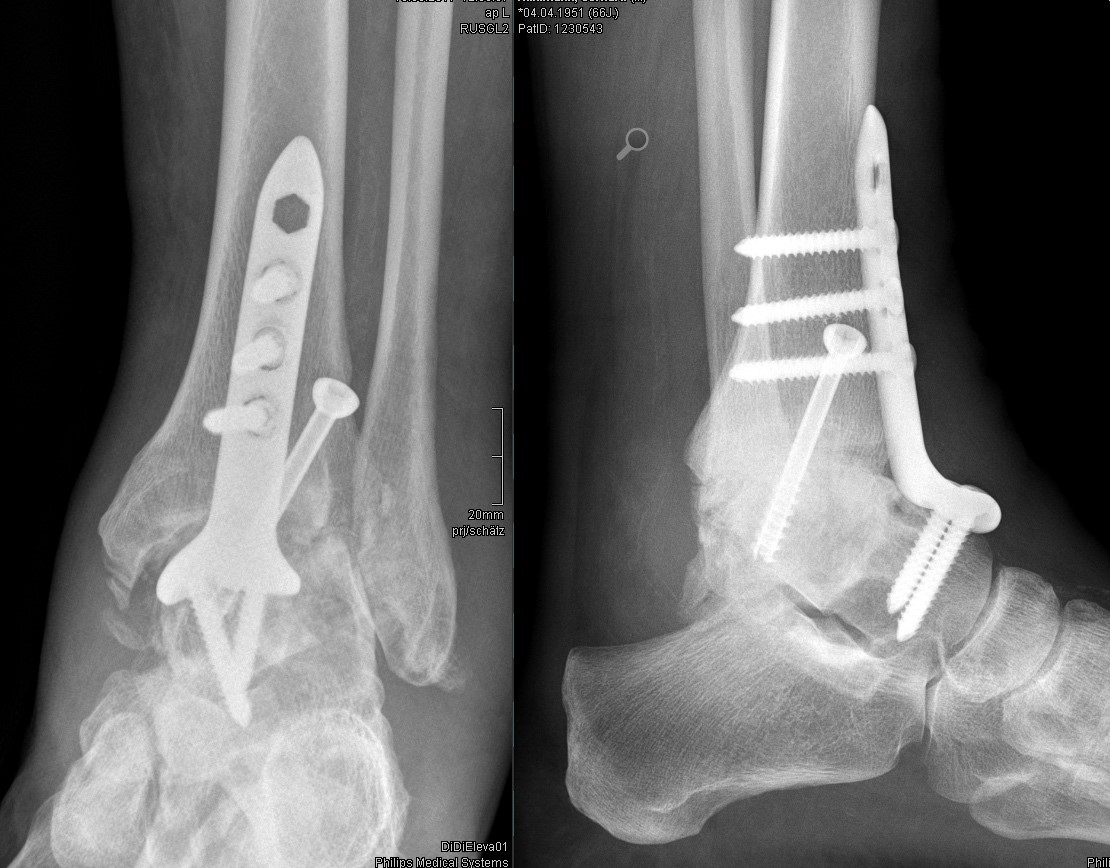

Postoperative Fehlstellungen

Schwere Knochenbrüche stellen eine große Herausforderung für der Operateur wie auch den Betroffnen dar. Heilungsverzögerungen aufgrund schwerer Begleitverletzung der Weichteile (z.B. offene Frakturn) resultieren nicht selten in Fehlstellungen. Diese können die Entwicklung von Arthrose fördern. Sie zu erkennen und ggf auch zu korrigieren erfordern modernste Methoden der OP Planung und Umsetzung wie auch große operative Erfahrung.